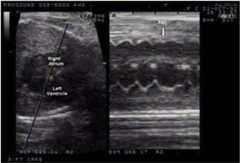

The diagnosis of fetal arrhythmias remains challenging. Routine obstetrical evaluation relies on auscultation and Doppler detection of pulsatile flow within the fetal heart. These techniques allow determination of the ventricular rate but are incapable of evaluating the AV relationship or the origin of the rhythm. M-mode echocardiography with simultaneous recording of the atrial and ventricular contractions is the primary modality for determining the atrial and ventricular relationship and rates (Fig. 1).

Fig. 1.

M-mode echocardiography with simultaneous recording of the atrial and ventricular contractions showing a premature atrial contraction (PAC) that did not conduct to the ventricle.